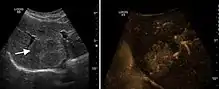

Hepatocellular carcinoma (HCC)

It is the most common liver malignancy. It develops secondary to cirrhosis therefore, ultrasound examination every 6 months combined with alpha fetoprotein (AFP) determination is an effective method for early detection and treatment monitoring for this type of tumor . Clinically, HCC overlaps with advanced liver cirrhosis (long evolution, repeated vascular and parenchymal decompensation, sometimes bleeding due to variceal leakage) in addition to accelerated weight loss in the recent past and lack of appetite.

HCC appearance on 2D ultrasound is that of a solid tumor, with imprecise delineation, with heterogeneous structure, uni- or multilocular (encephaloid form). An "infiltrative" type is also described which is difficult to discriminate from liver nodular reconstruction in cirrhosis. Typically HCC invades liver vessels, primarily the portal veins but also the hepatic veins . Doppler examination detects a high speed arterial flow and low impedance index (correlated with described changes in tumor angiogenesis). The spatial distribution of the vessels is irregular, disordered. CEUS examination shows hyperenhancement of the lesion during the arterial phase. During the portal venous phase there is a specific "wash out" of ultrasound contrast agent (UCA) and the tumor appears hypoechoic during the late phase. Poorly differentiated tumors may have a stronger wash out leading to an isoechoic appearance to the liver parenchyma during portal venous phase. This appearance was found in approx. 30% of cases. The described changes have diagnostic value in liver nodules larger than 2 cm.